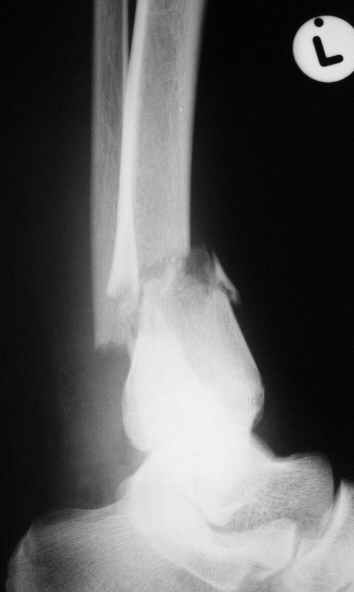

Уважаемые коллеги,Больной 17 лет , 3 недели с момента травмы, был переведен в наше отделение из соседнегогоспиталя.

Попытка закрытой ручной репозиции, предпринятая ранее в этой больнице,оказалась безуспешной, что и явилось причиной перевода к нам.Чтобы вы предложили в данной ситуации?Показана ли фиксация перелома малоберцовой кости в данном случае или в этом нет необходимости?Евгений Чекашкин

На прямой проекции видно угловое смещение отломков малоберцовой кости, обуславливающий и

наклон тарана, да и вальгус отломков б.б. , а на боковой проекции -смещение отломков

кпереди и по длине.